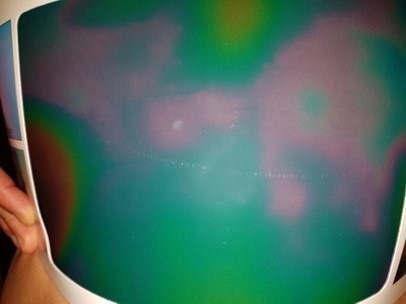

The color variation of black, red and blue was not statistically significant (figure 4). The variation to green went from 51% (20.25) pre-treatment to 62.25% (17.01) after treatment. This difference was statistically significant: p = 0.043.

Figure 4.Abdominal thermography (left flank). Range of colors displayed with the Thermoplate®30 (standard): blue, red and green.

A healthy thermographic picture, without cellulite, is homogeneous. The exact color of this situation of normality will be in the central area of the thermographic scale, but will depend on the plate used and the general conditions of the environment in which the measurements are taken. In this case, the homogeneous color seen in patients without cellulite was light green. The quantification of the color channels of the thermographic images showed some non statistically insignificant differences, but also significant and important color variations. The non-significant variation of the colors red and light blue is understandable, while these two colors represent intermediate categories in the thermographic scale. That is to say, that the decrease of a certain color (eg.: pink to green) can be compensated by the variation of another color (eg.: purple to pink). On the other hand, this study shows a significant variation towards the green and towards the homogeneity of the color. This, clinically, results in an improvement of cellulite and a reduction in edema, which is typically visualized as images of large, diffuse spots. These edematous spots and micro-nodules were visualized with different shades of red, purple and light blue.